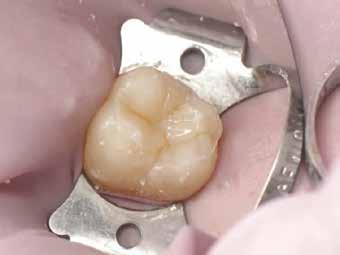

9. ábra: Hat hónapos kontroll.

12. ábra: A premoláris fogak preoperatív állapota.

13. ábra: A premoláris fogak postoperatív fotója.

14. ábra: Egy moláris fog preoperatív állapota.

15. ábra: Egy moláris fog postoperatív fotója.